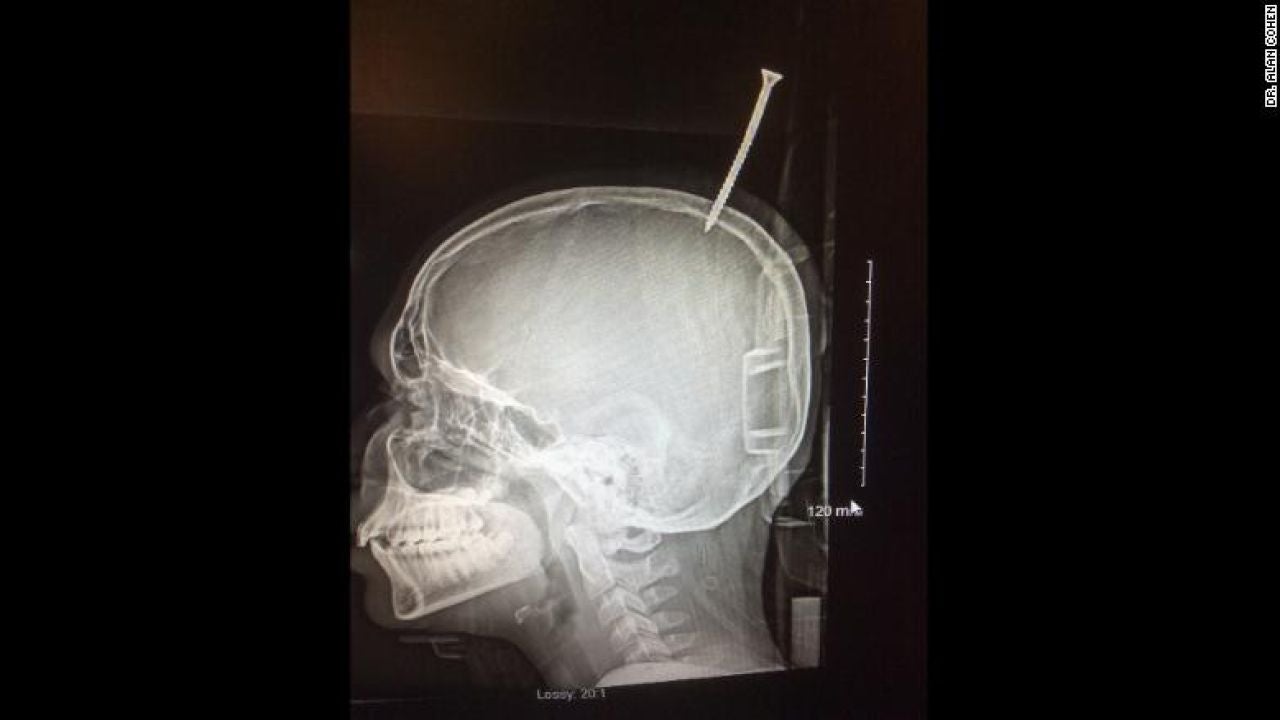

Radiografía del pequeño Darius en el hospitalDoctor Alan Cohen

El menor estaba construyendo una casa en un árbol en Maryland, EEUU, cuando un tornillo se le clavó en el cráneo. Un helicóptero tuvo que trasladarle de urgencia al hospital, donde los médicos aseguraron que si el tornillo se hubiera clavado un milímetro más, se habría desangrado.